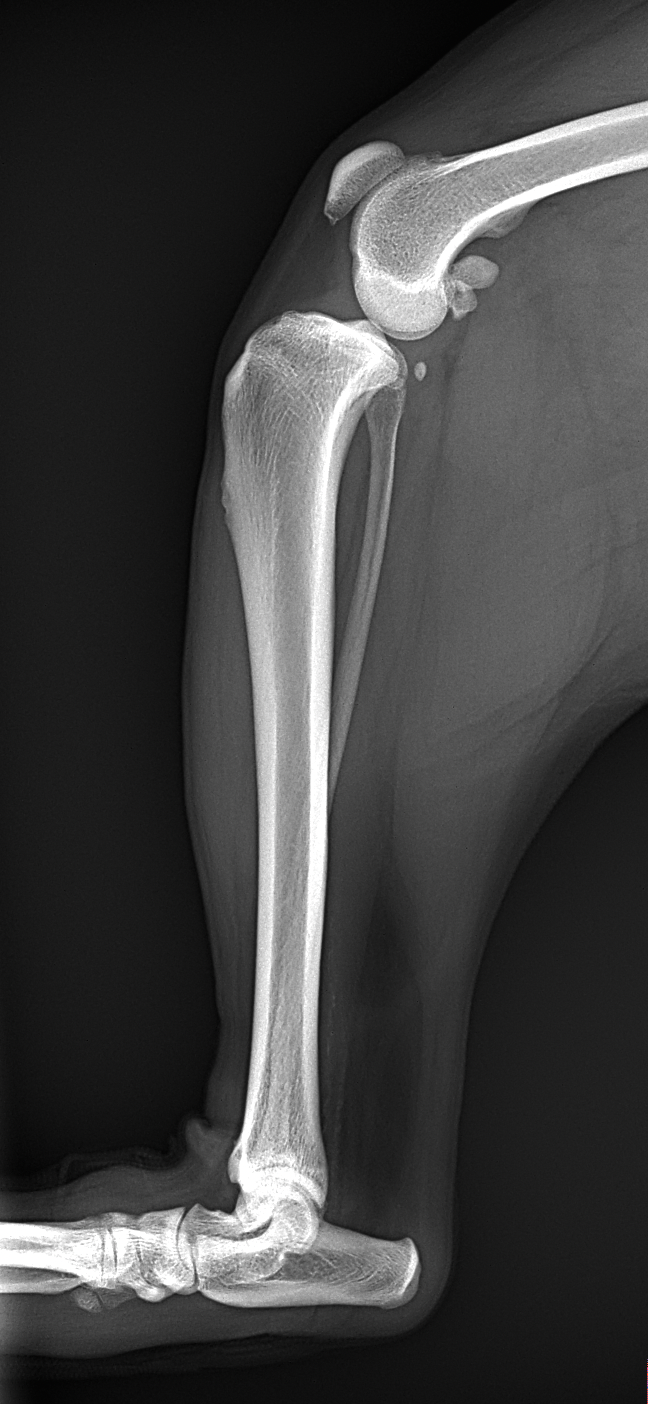

高齢犬が前十字靭帯を断裂し跛行を呈している。とのこと。

歩様検査:左後肢の非負重性~重度跛行

触診所見:膝関節不安定性(前方引き出し徴候 陽性)、脛骨前方スラスト(陽性)、脛骨ピボット圧迫試験(陽性)